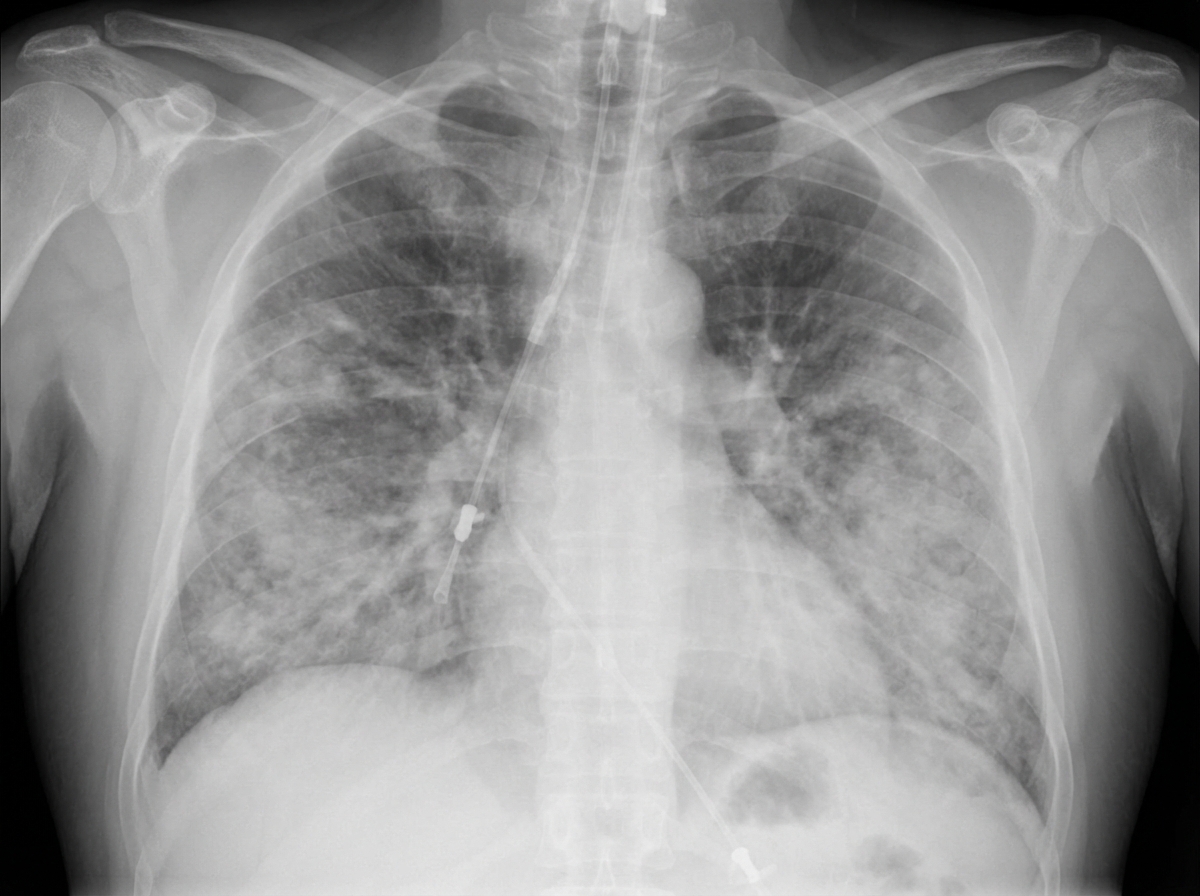

What is the pathophysiological cause of the disease shown in the X-ray and gross specimen from an ICU patient?

Explanation: ***Diffuse alveolar damage*** - **DAD** is the hallmark pathophysiological process of **ARDS** in ICU patients, characterized by **bilateral diffuse infiltrates** on X-ray and **heavy, firm, dark congested lungs** on gross examination. - Features **hyaline membrane formation**, **alveolar epithelial cell necrosis**, and **capillary endothelial damage** leading to increased vascular permeability and protein-rich edema. *Usual interstitial pneumonia* - **UIP** is a chronic fibrotic process with **honeycombing** and **subpleural distribution**, not the acute bilateral pattern seen in ICU settings. - Associated with **idiopathic pulmonary fibrosis** and shows **temporal heterogeneity** with areas of normal lung, inflammation, and fibrosis. *Acute interstitial pneumonia* - **AIP** (Hamman-Rich syndrome) presents similarly to DAD but is an **idiopathic** condition, not associated with the acute critical illness context of ICU patients. - Shows **diffuse alveolar damage** histologically but lacks the **identifiable precipitating factors** typically present in ICU-related ARDS. *Organizing pneumonia* - **OP** shows **intraluminal fibroblastic plugs** (Masson bodies) within **alveolar ducts and bronchioles**, creating a patchy rather than diffuse pattern. - Characterized by **preservation of lung architecture** and **good response to corticosteroids**, unlike the severe acute damage in ICU patients.